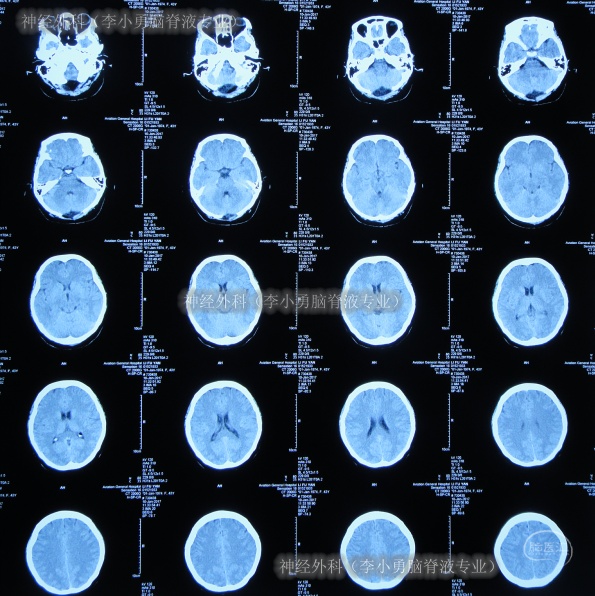

继续治疗1月余,头痛消失,期间3次查头颅CT(图-14)感染进一步变好。

图-14:期间3次查头颅CT